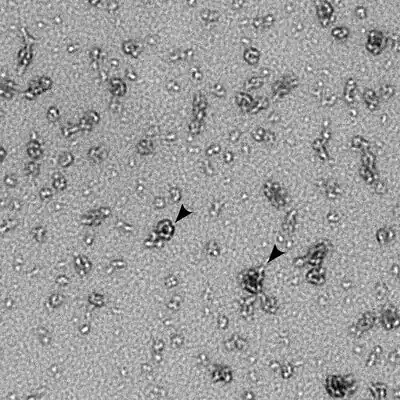

Chlamydia trachomatis is a gram-negative bacterium that can replicate only within a host cell.[3] Over the course of the C. trachomatis life cycle, the bacteria take on two distinct forms. Elementary bodies are 200 to 400 nanometers across, and are surrounded by a rigid cell wall that allows them to survive outside of a host cell.[3][4] This form can initiate a new infection if it comes into contact with a susceptible host cell.[3] Reticulate bodies are 600 to 1500 nanometers across, and are found only within host cells.[4] Neither form is motile.[4]

Like other Chlamydia species, C. trachomatis has a life cycle consisting of two morphologically distinct forms. First, C. trachomatis attaches to a new host cell as a small spore-like form called the elementary body.[5] The elementary body enters the host cell, surrounded by a host vacuole, called an inclusion.[5] Within the inclusion, C. trachomatis transforms into a larger, more metabolically active form called the reticulate body.[5] The reticulate body substantially modifies the inclusion, making it a more hospitable environment for rapid replication of the bacteria, which occurs over the following 30 to 72 hours.[5] The massive number of intracellular bacteria then transition back to resistant elementary bodies, before causing the cell to rupture and being released into the environment.[5] These new elementary bodies are then shed in the semen or released from epithelial cells of the female genital tract, and attach to new host cells.[6]